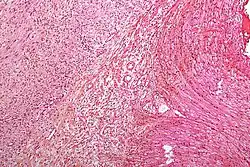

beriberi hypesthesia.